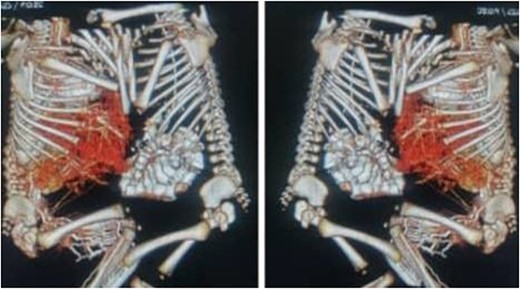

After anesthetic preparation and central line insertion, both twins were placed on sterile sheets and then prepped anteriorly, Incision was made using monopolar and bipolar diathermy in the connecting bridge, skin and muscle were cut, connections within parietal peritoneum were identified, and then carefully divided, followed by the connecting part of the liver (Fig. 2), after two and half hours of surgery the twins were finally separated and other twin was taken to another table.

Connections within parietal peritoneum were identified and then carefully divided, followed by the connecting part of the liver.